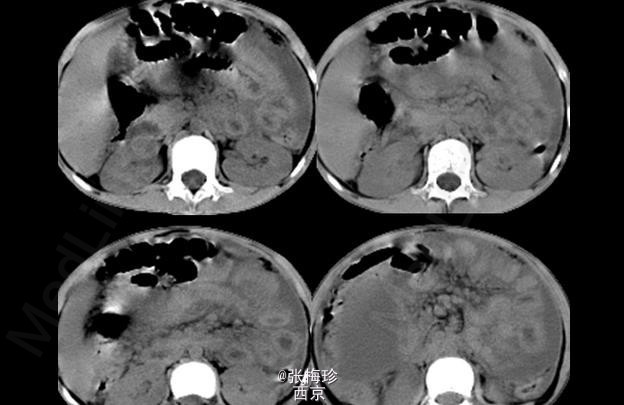

临床一例结核性腹膜炎

结核性腹膜炎

女,9岁,上腹闷痛伴腹水1年余前来就诊

查体:消瘦面容,腹膨隆,上腹部有轻压痛,无明显反跳痛,大小肿物,移动差

结核性腹膜炎 处理:药物治疗,足量、联合为治疗原则